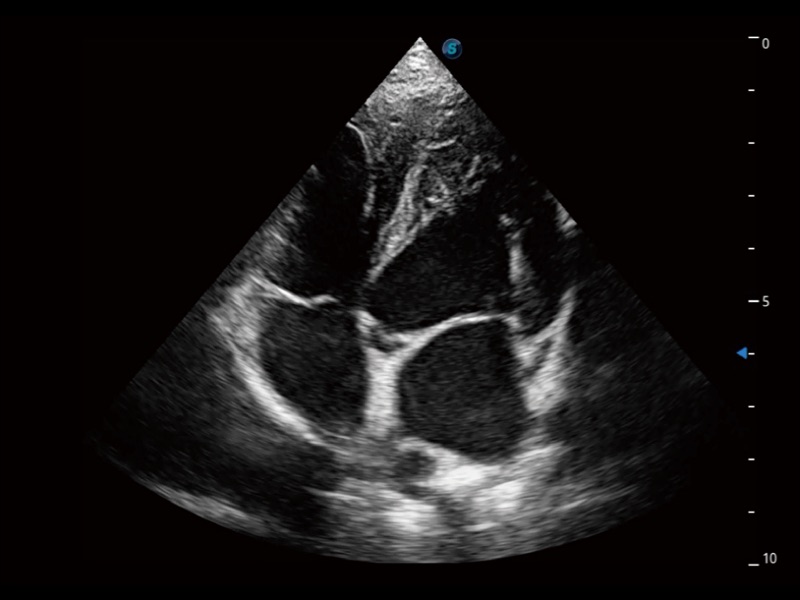

ProPet 70 进一步提升了微米成像算法,更加注重对基础原始图像的还原和保留,在有效减少斑点噪声、增强组织边界显示的同时,避免过度优化丟失真实的解剖信息。

通过360度任意调节3条M型取样线,在同一心动周期上观察心脏不同位置的运动曲线,得到准确的心功能测量数据,有效评估心肌运动及左心室功能。

实时用颜色表示心肌组织运动,观察和定量组织的运动情况,对快速检测与评估心肌的灌注和活性、电传导及心肌收缩和舒张功能等均能提供重要的诊断信息。

ProPet 70专为动物医生设计,对不同的动物体型和生理结构作出了针对性的优化。通过动物影像专用软件,可满足个性化的应用需求,帮助动物医生获得更精确的诊断数据。

当心脏测量结果超出正常范围时,可实时预警提示动物医生,减少疾病漏诊概率。